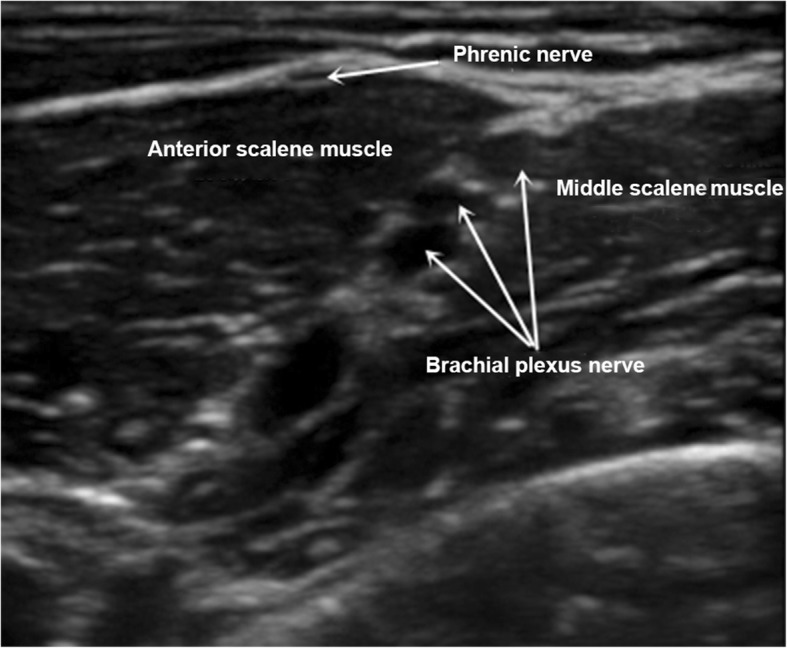

The patient involved has consented to the publication of her case and signed the consent form. A 70-year-old woman was hospitalized for third degree uterine prolapse in the First Affiliated Hospital of Guangzhou University of Chinese Medicine on February 10, 2016. Vaginal hysterectomy under continuous epidural anesthesia was indicated. She was rated class I risk using the American Society of Anesthesiologists (ASA) criteria and did not have any cardiopulmonary dysfunction or gastrointestinal disease. The preoperative blood tests were normal. The arterial blood pressure (ABP) was 145/85 mmHg. The peripheral oxygen saturation (SpO2) measured using pulse oximetry was 98%. The heart rate (HR) was 70 beats per minute. The results of the blood gas analysis, performed after the patient entered the operating room, were as follows: arterial partial pressure of oxygen (PaO2), 90 mmHg; and arterial partial pressure of carbon dioxide (PaCO2), 39 mmHg. The patient was placed in the left lateral position, and a continuous epidural anesthesia was performed in the L2 – L3 space. After successful puncture, a catheter was inserted in cephalad direction 4 cm beyond the tip of the needle. The patient was then placed in a supine position and given oxygen continuously via nasal catheter with an oxygen flow rate of 2 L/minute. A test dose of 3 mL 1.5% lidocaine was administered through the epidural catheter, followed by 8 ml of a 1.5% lidocaine-0.5% bupivacaine mixture. Sensory block was shown to be complete within 10 min, and the upper level of the block was at the level of T8. At this time, ABP was 130/70 mmHg, SPO2 was 99%, and HR was 82 beats per minute. A continuous intravenous infusion of dexmedetomidine 0.3 μg/kg/h was administered. The patient developed hiccups approximately 30 min after the start of surgery, about 10 times per minute at first, gradually increasing to 30 times per minute, 10 min later. At this time, ABP was 150/90 mmHg, SPO2 was 98%, and HR was 90 beats per minute. The persistent hiccups interrupted the operation. In order to terminate the hiccups, we first used repeated CO2 inhalation for 5 min, followed by intravenous injection of 25 mg chlorpromazine and 20 mg metoclopramide. There was no effect after 20 min. The abnormal movement of the diaphragm was confirmed using an ultrasound examination. It showed a spastic contraction of the patient’s right diaphragm. We decided to block the right phrenic nerve under the guidance of a high resolution portable ultrasound unit (Italy, Yum Mylab One). With the patient’s head towards the left, the ultrasound probe (frequency, 8 MHz) was placed on the right side of the neck. The axial scanning of the neck along the surface of the anterior scalene muscle, showed that the phrenic nerve rounded the anterior scalene muscle from the outside to the inside, and coursed through the trench between the common carotid artery and anterior scalene muscle (Fig. 1). Using an in-plane technique, when the needle was close to the phrenic nerve, 5 ml 0.4% ropivacaine was injected around the phrenic nerve. The hiccups gradually stopped after approximately 5 min. At this time, ABP was 135/75 mmHg, SPO2 was 99%, HR was 72 beats per minute, PaO2 was 88 mmHg, and PaCO2 was 41 mmHg. The patient reported no discomfort, and no related complications were observed. The operation resumed and ended 80 min later. The patient was kept in the intensive care unit for 24 h and was discharged 7 days after the surgery. No hiccups or phrenic nerve block-related complications were observed after the operation. No related complications were reported on the telephonic follow-up one month after being discharged.

Fig. 1.

The phrenic nerve ultrasonography of the right neck